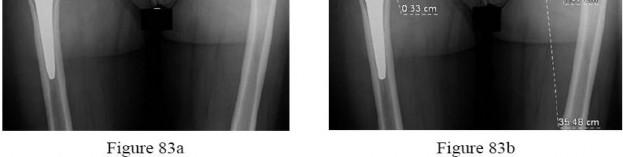

Explanation

The radiograph shows a large area of osteolysis involving the proximal femur. The implants appear solidly fixed on radiographs and, in the absence of symptoms, it is unlikely the implants are loose or infected. Although infection or metastatic disease is a possibility, the normal ESR and CRP values make the diagnosis of deep infection unlikely. The most likely cause for the radiographic findings is wear from metal particles resulting in an adverse local tissue response and osteolysis.